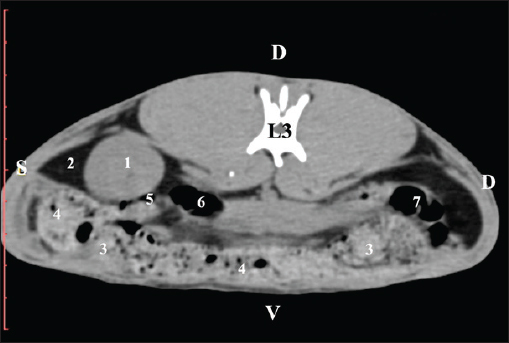

Pre-contrast CT at the Th13 level revealed the right kidney’s extremitas cranialis as a normoattenuated homogeneous soft tissue against the hypoattenuated margins of the lobus hepatis dexter and lobus caudatus (proc. caudatus). Ventrally, the right kidney was in contact with the duodenal par descendens, ileum, and cecum (Fig. 1).

Fig. 1. Pre-contrast computed tomography (CT) anatomical scan of the regio abdominis cranialis at the Th13 level. (1) Lobus hepatis dexter; (2) ren dexter; (3) lobus caudatus (proc. caudatus) with visceral adipose tissue; (4) pars descendens of the duodenum; (5) ileum; (6) gl. adrenalis dextra; (7) colon ascendens; (8) cecum; (9) colon transversum; (10) colon descendens; (*) 13th rib.